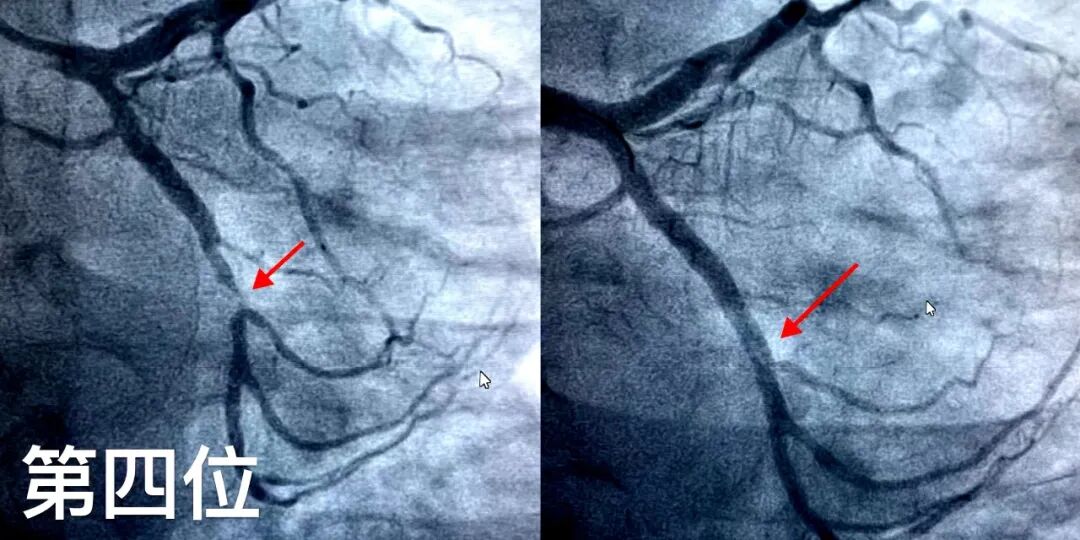

第三位患者为74岁男性,因活动后胸闷气短、后背部疼痛,曾在外院就诊,诊断为急性非ST段抬高型心肌梗死。患者高度认可桓台县妇幼保健院心血管诊疗实力,主动要求转入行PCI治疗。术中造影证实,“罪犯血管”同样为左前降支。桓台妇幼心内科医疗团队不负信任,顺利完成介入手术操作。